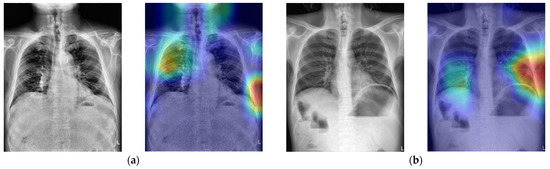

In order to verify if the proposed CNN model uses the correct spatial features to make a decision, Figure 8 shows the Grad-CAM-produced heatmaps of four selected TP cases. In Figure 6a–c, the red regions (higher weights) almost appear on the lesions of PPU. This result implies that all three CNN models could learn the spatial relationship between lesions and the other normal tissues in the X-ray image.

Figure 8. The heat map results of using three different CNNs on four selected TP cases (ad). The red arrows in the first column indicate the lesion. The red areas in the 2nd to 4th columns are the regions where the CNN predicted them as positive cases.